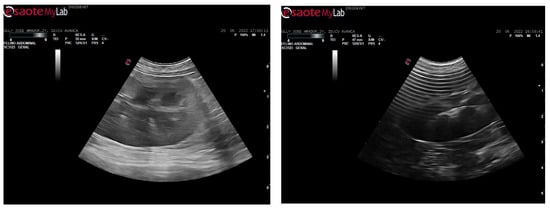

After 24 h, a hematoma began to form on the inner thigh, with a small area of skin in the center starting to necrose. In the following days, the limb became more edematous, the area of necrotic skin increased, and the animal remained prostrate. However, its temperature was within normal values. An ultrasound was performed (Figure 3), where a slightly hypoechoic pancreas and a slight generalized peritoneal reaction were observed.

Figure 3. Abdominal echography with hypoechoic pancreas and slight generalized peritoneal reaction in a cat bitten by a venomous snake.